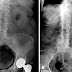

Due to the atypical presentation and rarity of the infection, it takes a physician longer to diagnose than more common types of bladder infections. Diagnosis requires a personalized investigation with consideration to risk factors and symptoms (Bobba). Radiology of the abdominal or pubic region has proven to be an important tool in reaching a definitive diagnosis of conditions causing gas in the urinary tract. Computer tomography, or CT scans, are of most help due to their high sensitivity in detecting gas and air bubbles (Gheonea, Bondari). However, radiology is normally not the first tool used to diagnose. Most diagnoses are made by chance after imaging examination (Weerakkody). Sometimes, even when patients don't show symptoms, their Emphysematous cystitis infection level can be very advanced already (De Baets, Baert). Gas in the bladder wall will often have the appearance of cobblestone or a "beaded necklace" with the use of conventional radiography (Weerakkody). Delayed diagnosis can lead to a severe infection, extension of the uterus, rupturing of the bladder, and death. Emphysematous cystitis has an overall mortality rate of 7%. However, surgery is only considered in severe cases where the disease progresses involving the ureters, kidneys, or adrenal glands. When required, surgery may be extensive. (De Baets, Baert).